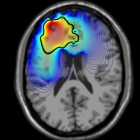

Mae'r grŵp yn defnyddio'r technegau mathemategol a chyfrifiannol diweddaraf i fynd i'r afael â phroblemau ymchwil o'r biowyddorau, gwyddorau bywyd a meddygaeth. Ein nod yw datblygu modelau mathemategol ac ystadegol rhagfynegol a dulliau cyfrifiannol i fynd i'r afael â chwestiynau cyfoes sy'n berthnasol i gwestiynau biolegol.

Rydym yn datblygu ac yn dadansoddi dulliau cyfrifiadurol a rhifol arloesol, gan astudio eu defnydd mewn meysydd amrywiol megis Topoleg Gyfrifiadurol, Gwyddor Data, Damcaniaeth Medrydd Dellt, Bioleg Fathemategol, Ymchwil Canser a Geometreg Algebraidd Gynhwysol.